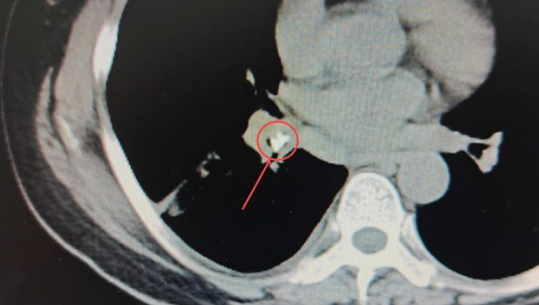

在CT影像中能夠很清晰地發(fā)現(xiàn):患者右肺葉已經(jīng)出現(xiàn)大面積實(shí)變[1],形成“白肺”(正常的肺葉組織在CT影像中呈黑色),在右肺基底段的一截支氣管中,有一個(gè)類似鈣化的“亮點(diǎn)”。醫(yī)生們進(jìn)一步仔細(xì)查看,發(fā)現(xiàn)這個(gè)亮度極高的異物顯示出的密度與骨骼的密度相近。

安女士肺部CT影像中極不尋常的“亮點(diǎn)”,馬上成為醫(yī)生們高度關(guān)注的疑點(diǎn),這也進(jìn)一步印證了礦總呼吸科專家做出的推斷:果然有異常的東西滯留肺內(nèi),才導(dǎo)致患者如此嚴(yán)重的咳喘癥狀。

▼紅圈內(nèi)即卡在肺內(nèi)的異物

孟醫(yī)生說:“病人原本的右肺有三葉,從CT中能明顯看出其中一葉完全實(shí)變,張不開。如此大面積的肺實(shí)變?nèi)绻荒芗皶r(shí)疏通,很可能導(dǎo)致后期肺器官的萎縮,整個(gè)肺下葉都會(huì)跟著喪失呼吸功能的?!?/p>